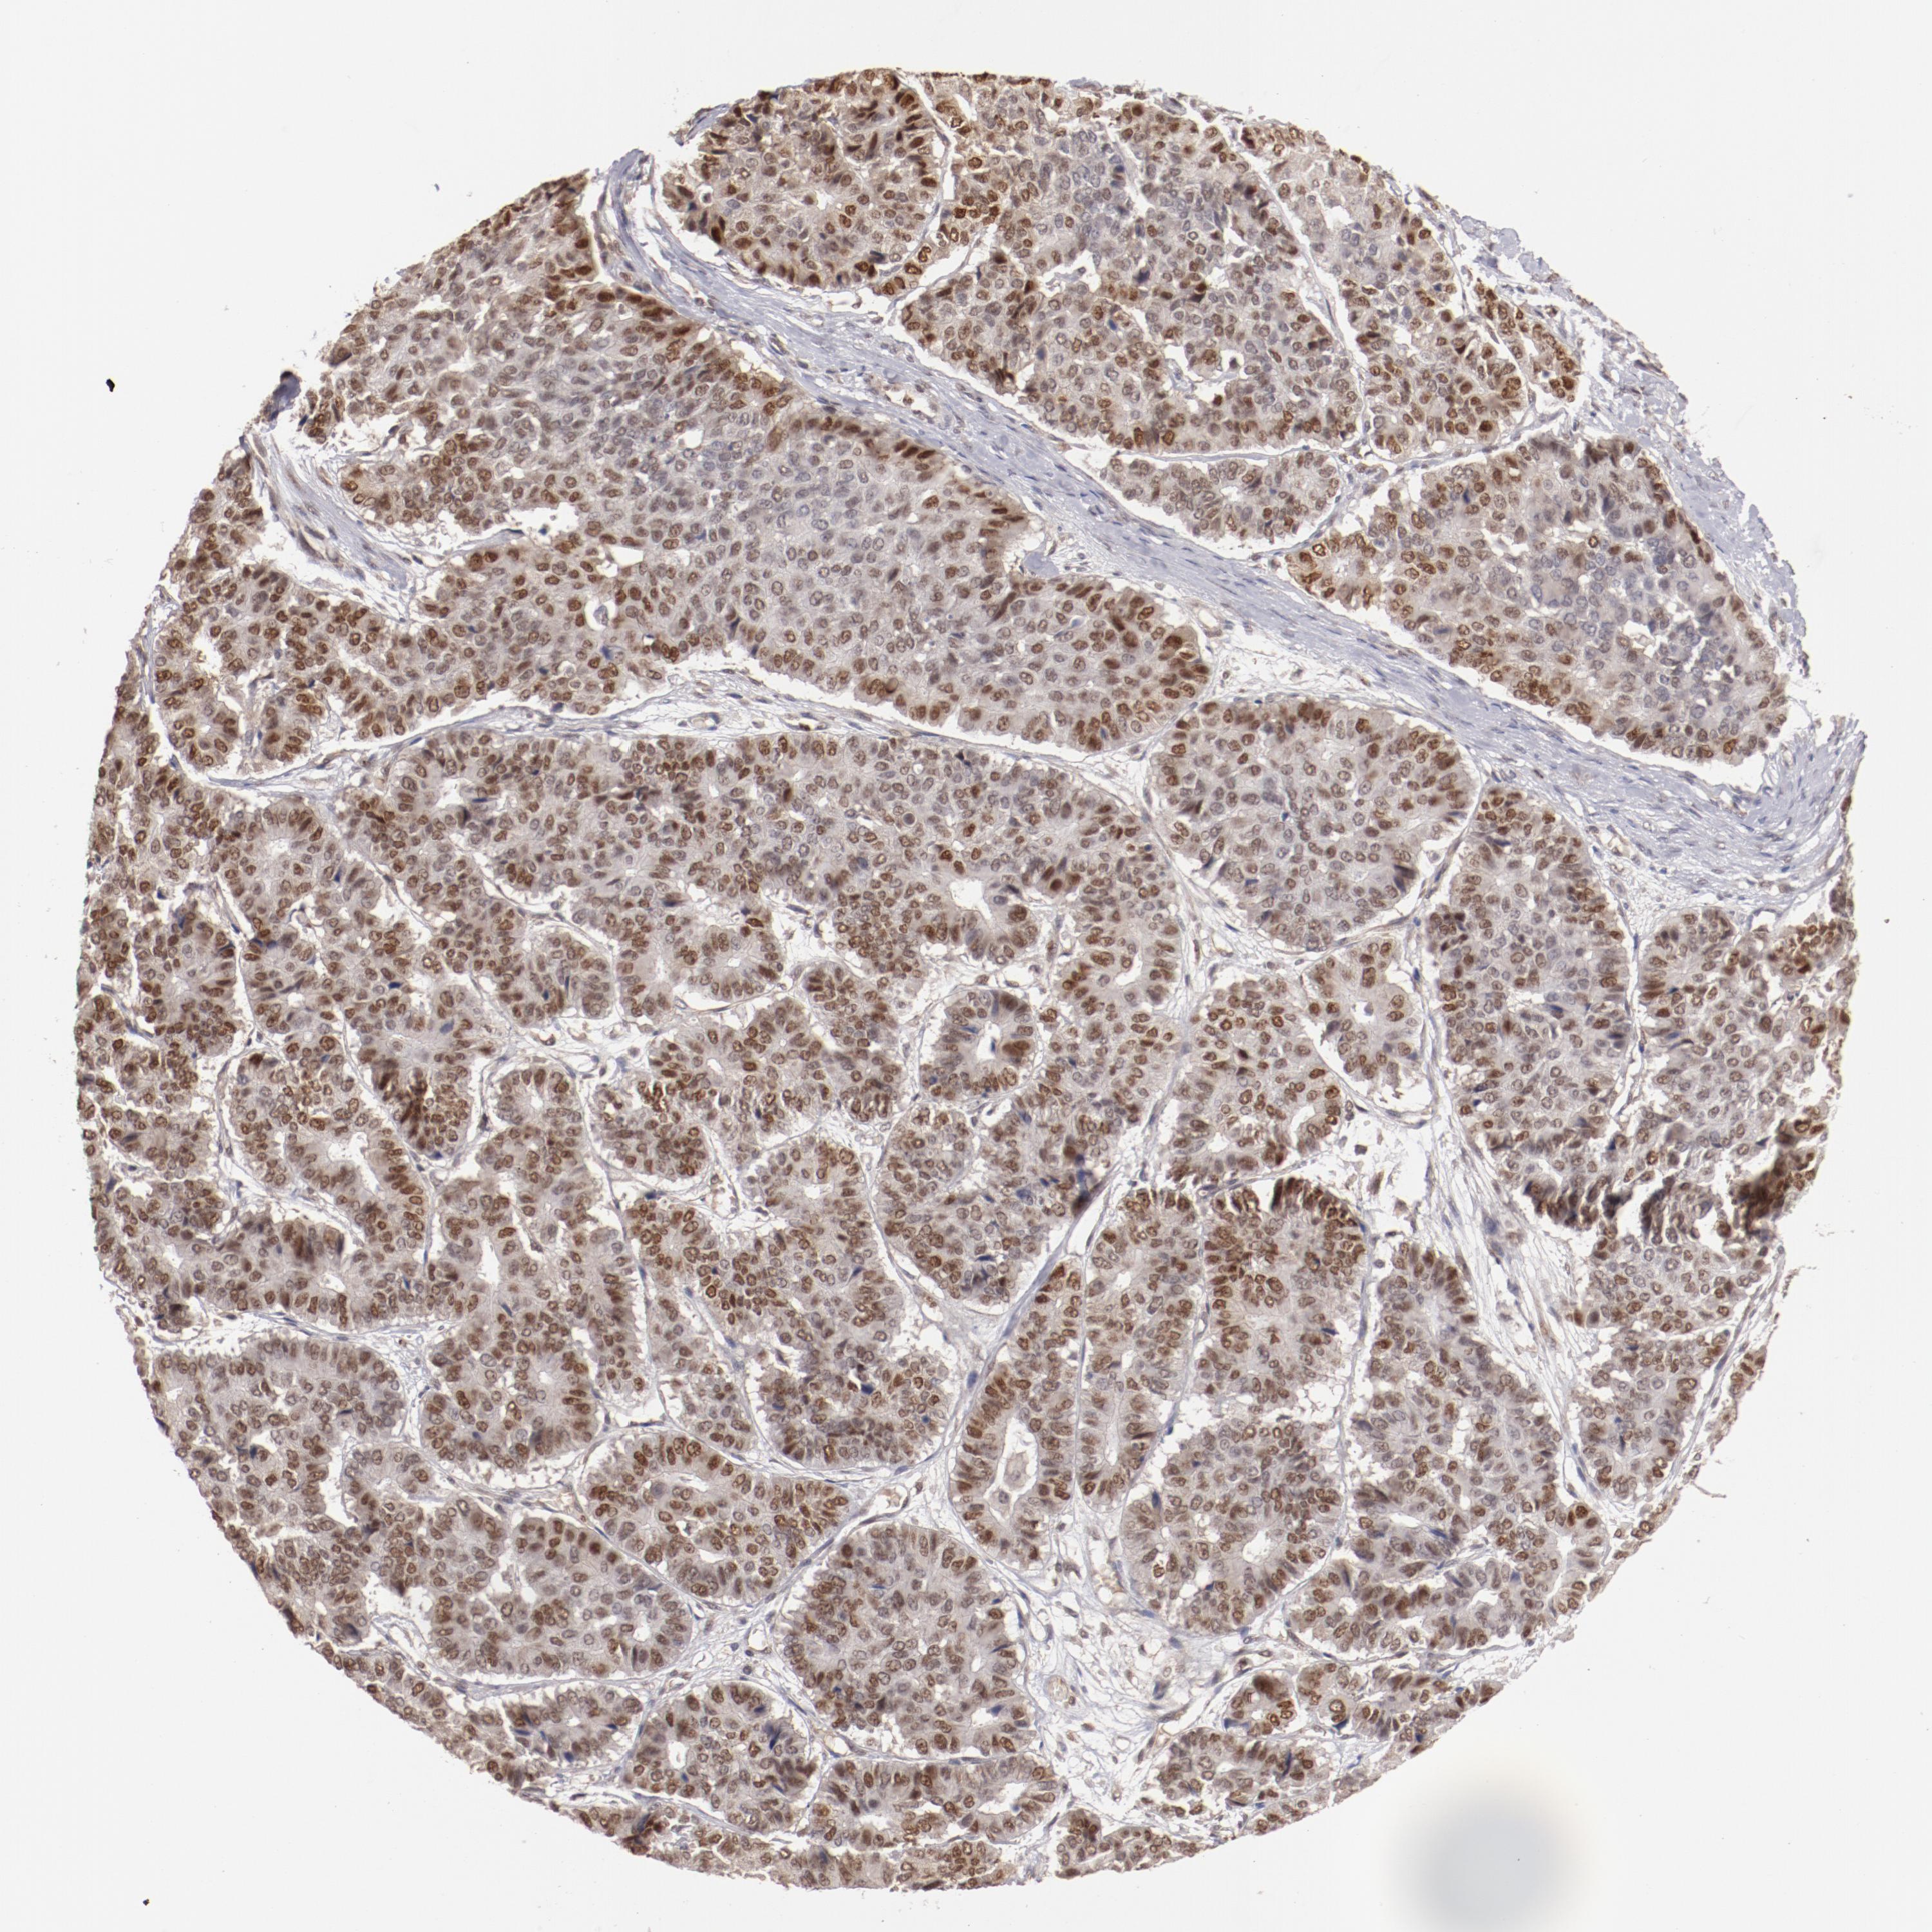

PANCREATIC CANCER - Protein expressioni

A mouse-over function shows sample information and annotation data. Click on an image to view it in a full screen mode. Samples can be filtered based on level of antibody staining by selecting one or several of the following categories: high, medium, low and not detected. The assay and annotation is described here.

Note that samples used for immunohistochemistry by the Human Protein Atlas do not correspond to samples in the TCGA dataset.

Antibody stainingi

Antibody staining in the annotated cell types in the current human tissue is reported as not detected, low, medium, or high, based on conventional immunohistochemistry profiling in selected tissues. This score is based on the combination of the staining intensity and fraction of stained cells.

Each image is clickable and will lead to virtual microscopy that enables deeper exploration of all samples and also displays staining intensity scores, fraction scores and subcellular localization as well as patient and tissue information for each sample.

Antibody HPA001914

Staining

High

Medium

Low

Not detected

Intensity

Strong

Moderate

Weak

Negative

Quantity

>75%

75%-25%

<25%

None

Location

Nuclear

Cytoplasmic/membranous

Cytoplasmic/membranous,nuclear

Adenocarcinoma, NOS

Adenocarcinoma, metastatic, NOS